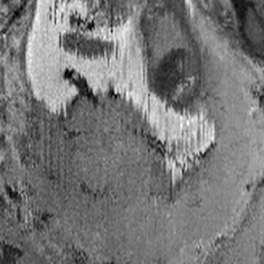

During image acquisition the fetus is not sedated and moves freely as well as the mother breathes normally. As a result, movements are likely to corrupt the scans, hiding pathology and causing overlap between different anatomical regions. In order to limit these artifacts, fast scanning sequences such as ssFSE [10] allow for the rapid acquisition of single slices at high in-plane resolution in a large field of view and good tissue contrast of the uterus. However, when acquiring a 3D volume through a stack of slices, inter-slice artifacts in the out-of-plane views are highly likely. Consequently, this restricts reliable diagnostics to individual slices in the current clinical practice. Fig. 1 depicts a typical example of motion related artifacts in a fetal single-shot fast spin echo (ssFSE) scan. The observed motion (c.f. Fig. 1 b & c) is of unpredictable nature and consists of a combination of maternal respiration movements, fetal movements and bowel movements.

Reconstruction of Fetal Organs: Exemplary PVR and SVR reconstructions under motion introduced by kicking of the fetus are shown in Fig. 11. PVR reconstruction results show an improved visual appearance and less blurring in the region with severe motion artifacts (arrow). An example of a challenging clinical case with a kidney malformation in one of twin fetuses, is shown in Fig. 8. Our clinical partners confirmed that such complications are easier to examine and to quantify after PVR-based reconstruction.